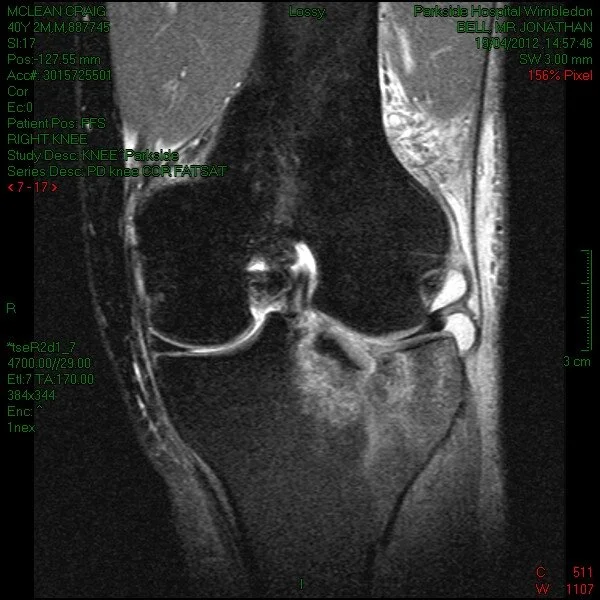

Below are images of my knee break (tibial plateau fracture), the shot of my puffy swollen leg 24 hours after the injury and the money shot – after surgery with a plate and 7 screws. Click on any image to enlarge.

I finally made it back from Canada after a few delays in dealing with insurance companies and airlines and went straight to Parkside hospital for MRI and CT scans it was then the the true extent of the damage was discovered. What looked like a fairly clean break on the X-ray at Banff hospital, turned out to be a fairly messy break. The only good news from the scans was the knee ligaments were intact. So I had a couple of days to get the swelling down from the flight for surgery in a few days.